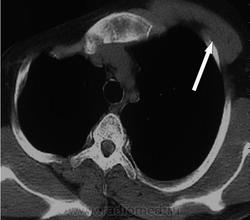

Синдром Поланда (СП) представляет собой комплекс пороков, включающий отсутствие большой и малой грудной мышц, синдактилию, брахидактилию, ателию (отсутствие соска молочной железы) и/или амастию (отсутствие самой молочной железы), деформацию или отсутствие нескольких ребер, отсутствие волос в подмышечной впадине и снижение толщины подкожно-жирового слоя. Отдельные компоненты этого синдрома впервые были описаны Lallemand LM (1826) и Frorier R (1839). Однако назван он по имени английского студента-медика Alfred Poland, который в 1841 году опубликовал частичное описание данной деформации. Полную характеристику синдрома в литературе впервые опубликовал Thompson J в 1895 году.

Слева нет тени большой грудной мышцы и это 100-пудово Поланд?